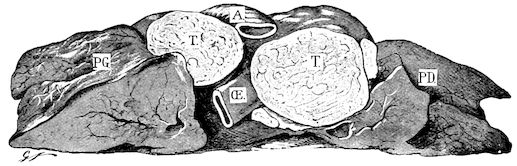

Fig. 8.—Transverse section through the middle region of the face in a pig suffering from osseous cachexia.

18In the final stages, the bones may be cut with a knife, and a time arrives when bony tissue seems completely to have disappeared; thus, as shown in Fig. 8 herewith, it was possible to cut the entire head of a pig into thin slices without the slightest difficulty. All parts of the head had been affected by the softening change.

From the chemical point of view, the diminution in mineral salts and in phosphate of calcium has long been recognised, but the degree of this change varies according to the phase. In human beings the proportions have been estimated as follows: Normal bone, 50 to 80 per cent. of phosphate of calcium; bone in persons suffering from osteomalacia, 5 to 20 per cent. of phosphate of calcium. The changes in the ossein have not been carefully studied. We only know that histologically the ossein becomes fibrillar, and that chemically it no longer retains its normal composition.